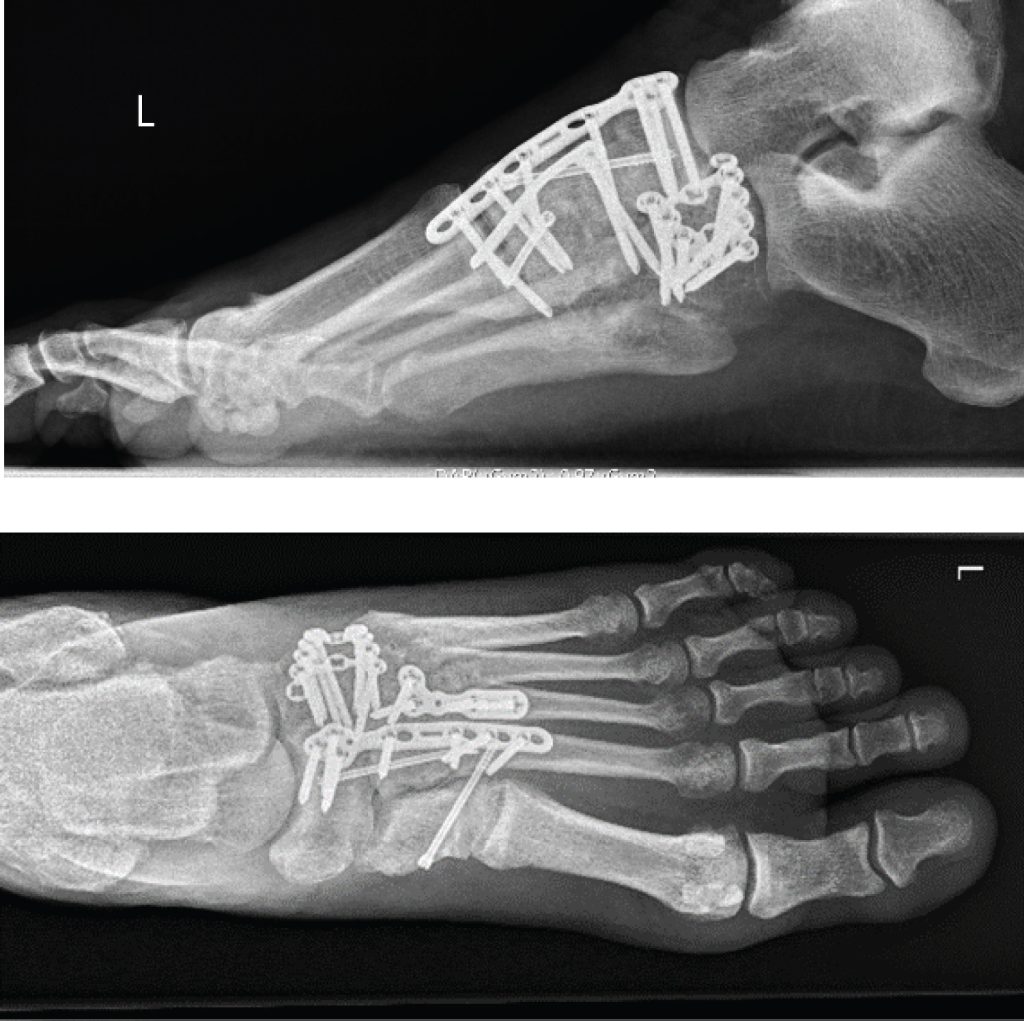

Unstable Lisfranc injuries result in displacement of some or all the tarsometatarsal joints with associated ligament rupture and/or significant fractures. Unstable injures are commonly managed operatively where the bones are fixed with screws, pins, or k-wire to allow for the injury to heal in a stable position. Fusion of this joint is also another operative management option.

Surgery is typically recommended for all injuries with a fracture in the joints of the midfoot or with abnormal positioning (subluxation) of the joints. The goal of surgical treatment is to realign the joints and return the broken (fractured) bone fragments to a normal position, via Internal fixation. Delaying surgical treatment if needed is associated with poor functional outcomes (Welck, Zinchenko, & Rudge, 2014). In this procedure, the bones are positioned correctly (reduced) and held in place with plates or screws. Because the plates or screws will be placed across joints that normally have some motion, some or all this hardware may be removed typically around the 8 week post-op mark however this is at the surgeon’s discretion.